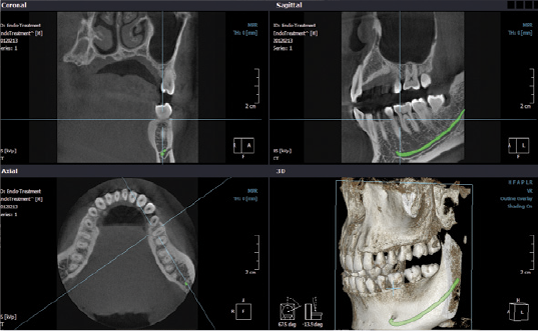

La TAC Cone Beam 3D è una moderna metodologia diagnostica in grado di riprodurre sezioni e di generare un’immagine tridimensionale del cranio (o di alcune sue parti) per mezzo di radiazioni acquisite da un sensore digitale ed elaborate da un computer.